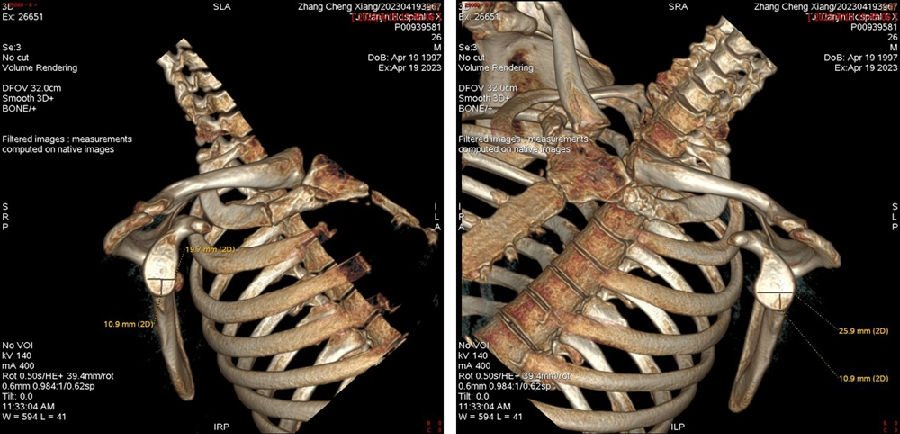

双侧CT三维扫描显示:健侧肩胛盂宽度D=25.9,患侧D=23.9,患侧肩胛盂骨性缺损d=6.2,骨性盂唇缺损面积d/D为23.9%(<25%)。肩胛盂轨迹GT(83%D-d)为15.3mm。

图28双侧CT三维扫描

图29 Hill-Sachs间隙为13.8mm(<15.3mm)

图30 评估结果

评估报告提示:右肩胛骨关节盂前下缘撕脱骨折,符合骨性bankart损伤。右肱骨头后上缘凹陷骨折,符合Hill-Sachs损伤。Hill-Sachs间隙为13.8mm(<15.3mm),为轨迹内肩关节前脱位。